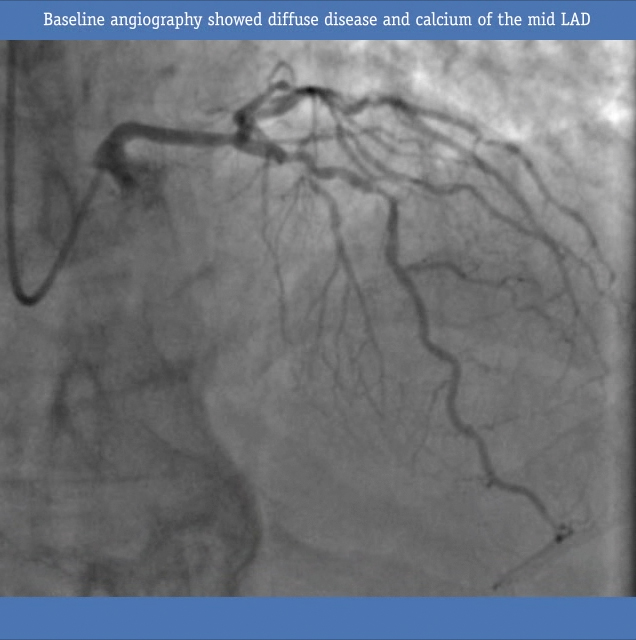

• Baseline angiography showed diffuse disease and calcium of the mid LAD